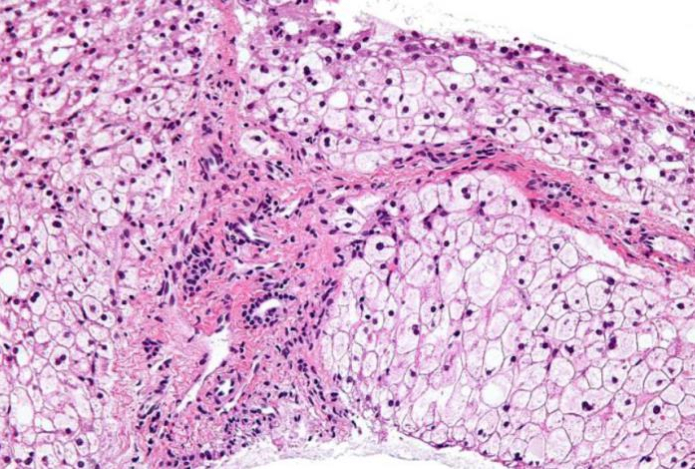

Раньше это называлось «триада смерти», сейчас мы называем это «метаболический синдром». В его основе лежит неалкогольная жировая болезнь печени — НЖБП.

Поэтому в науке я пропагандирую на старте диетотерапию, безусловно, под контролем печёночных трансаминаз, ультразвука, когда человек снижает вес за счёт уменьшения внутреннего висцерального жира.

Это основа кардиопротекции, что раньше ассоциировалось с возрастом. А сейчас приходят молодые мальчики, девочки 18-20 лет, с ожирением, диабетом второго типа, давлением. Половина этих метаболических заболеваний уходят от снижения висцерального веса. Надо не просто похудеть, а похудеть за счёт уменьшения внутреннего жира в печени, снизить жировой гепатоз.